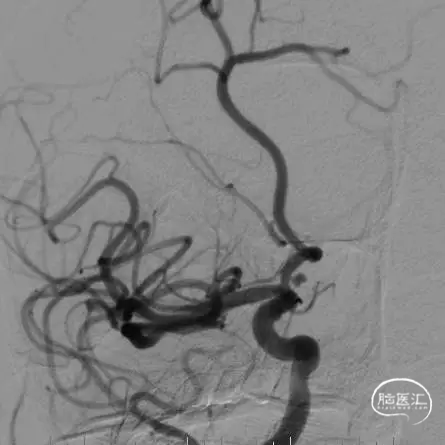

术前影像

栓塞过程

经微导管送入第一枚Jasper®SS弹簧圈,可见弹簧圈十分柔软,瘤体及瘤颈成篮满意。后送入Jasper®SS弹簧圈,微导管给予一定张力后,头端摆动良好,无明显踢管现象,瘤体栓塞满意。